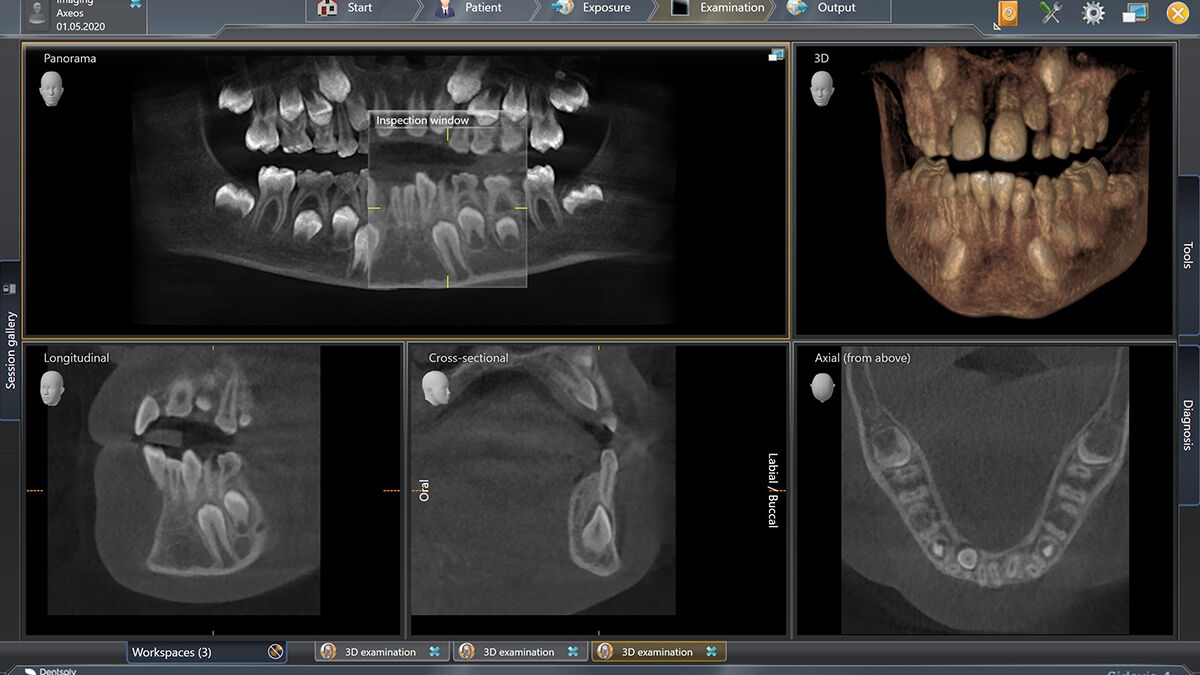

3D示例图

3D低剂量适应症实例